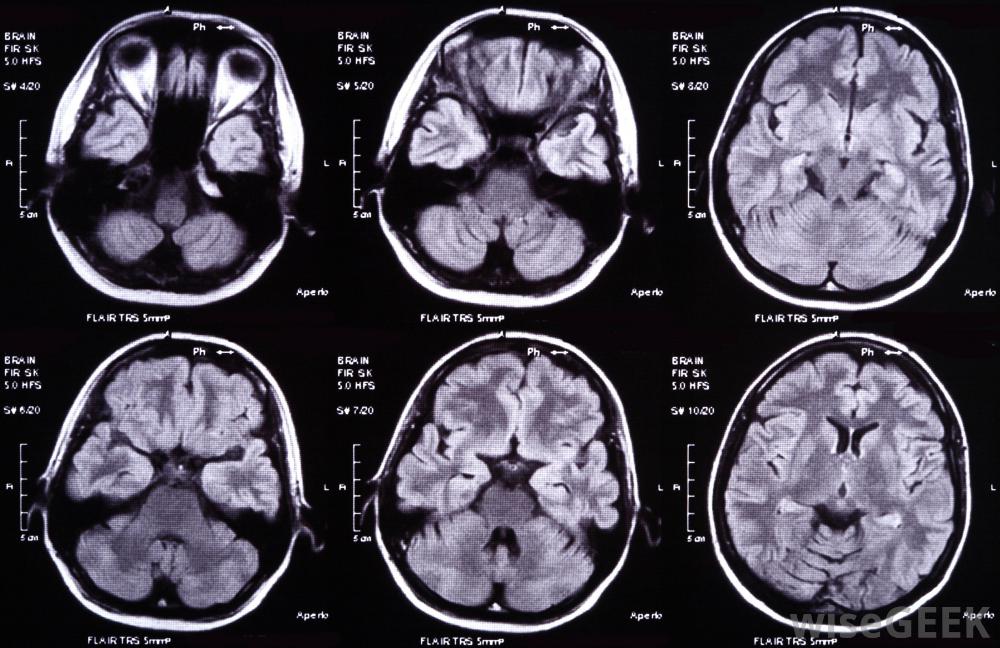

通过研究功能磁共振脑扫描,医生可以准确地确定情绪变化和情绪触发因素生物反馈最令人惊讶的发现是"自主"神经系统的各个方面都可以接受有意识的控制戈登,耶鲁大学著名心理学家和神经科学家。他让老鼠改变各种神经功能,从心率到脑波,通过有选择地直接刺激他们的快感中枢来奖励他们。已经被科学证明和复制的生物反馈可以严重帮助治疗失禁、中风和脊髓康复,压力和疼痛管理。生物反馈装置比你想象的要普遍得多——例如,甚至镜子和浴室秤,都是生物反馈的形式,可以向我们传递关于我们的外貌或体重的信息。从这个意义上说,每个人都使用生物反馈人们希望生物反馈对治疗焦虑、抑郁、毒瘾、头痛等都是有用的,还有一些人想利用生物反馈装置提升到瑜伽士般的控制自己身体功能的水平。有人建议,实时功能磁共振成像(fMRI)脑部扫描可以让我们在生气或困惑时立即注意到,使我们更倾向于思考这些情绪如何影响我们的决定和想法。